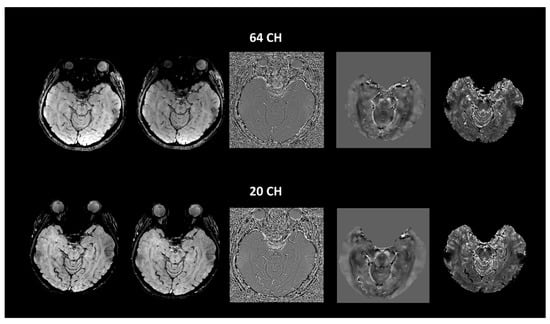

2.2. Imaging Protocols

2.3. Imaging Data Analyses